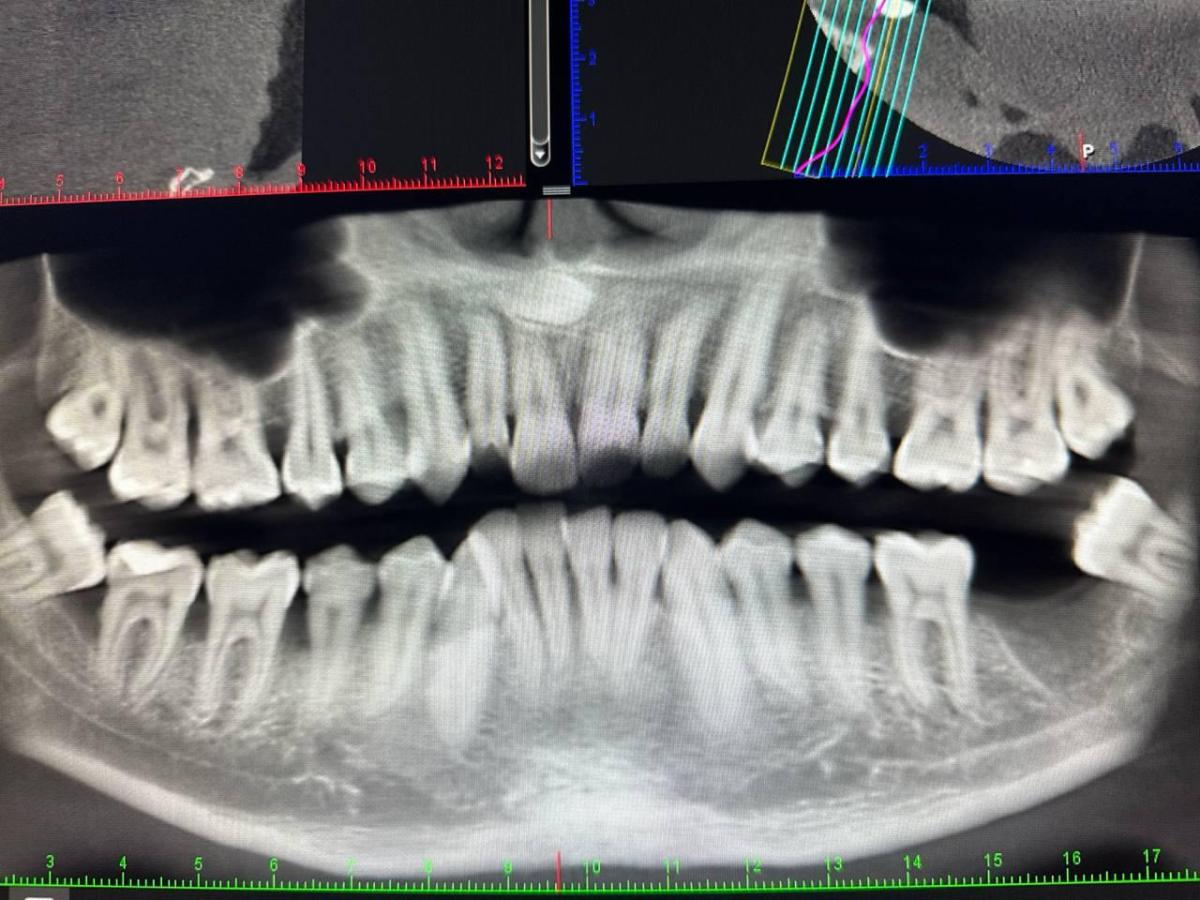

Интересует мнение по 47 зубу. Пару дней назад откололся кусочек пломбы. Присутствуют неприятные ощущения. Терапевт сказала, что нужно лечить и скорее всего с удалением нервов + пломбированием каналов с последующей установкой пломбы.

Хирург склоняется сразу к удалению ввиду того, что убыль костной ткани значительная и смысла лечить нет.

Парадонтолог месяц назад сказал, что 47 зуб рекомендован к удалению так как убыль костной ткани дошла до корней. Но он сторонник того чтобы побороться за зуб и не удалять его.